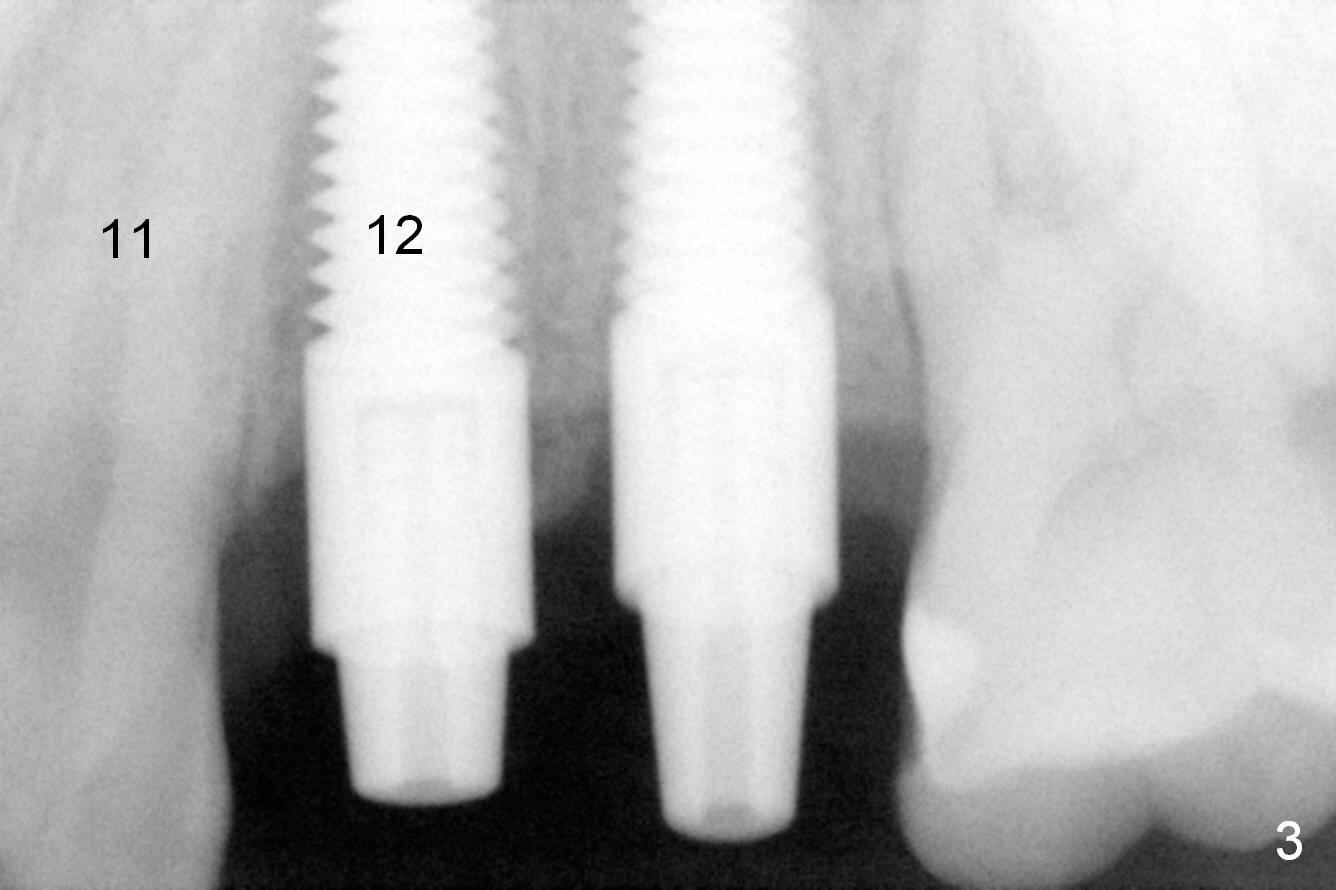

Taking 2 additional PAs with sensor 1 is frustrating (Fig.1,2), no apices shown. Osteotomy is done smoothly with 2 mm pilot drill at 20 mm, 2.5 mm reamer at 17 mm, and 3 mm reamer at 14 mm and 4.5x20 mm tap at 17 mm. The 1st intraop PA is taken with sensor 1 when 2 of 4.5x20 mm implants are placed (Fig.3); the implant at #12 is close to the root of the tooth #11. The 2nd PA is taken with sensor 2: the apex of #11 touches the implant at #12 (Fig.4). There is no separation when panoramic X-ray is taken (Fig.5). Effort is exerted to re-direct the osteotomy twice (Fig.6: tap; Fig.7: implant) without success. When the implant is removed, a PA is taken; it appears that the root of the tooth #11 has no damage (Fig.8). To obtain the best recovery, socket preservation is carried out with 50/50 cortical/cancellous allograft mixed with Osteogen (Fig.12 *) and Collagen Dressing (Fig.9: #12). A 2 (or 3)-unit provisional bridge (Fig.10: #12,13) is fabricated over the implant (Fig.9 I)/abutment (A) to cover these 2 sockets. After acid etching #11 D surface (Fig.9 >) and relining (Fig.11 *), the provisional bridge is bonded to the tooth #11 (Fig.11,12 black >) so that bone graft will be less likely dislodged.